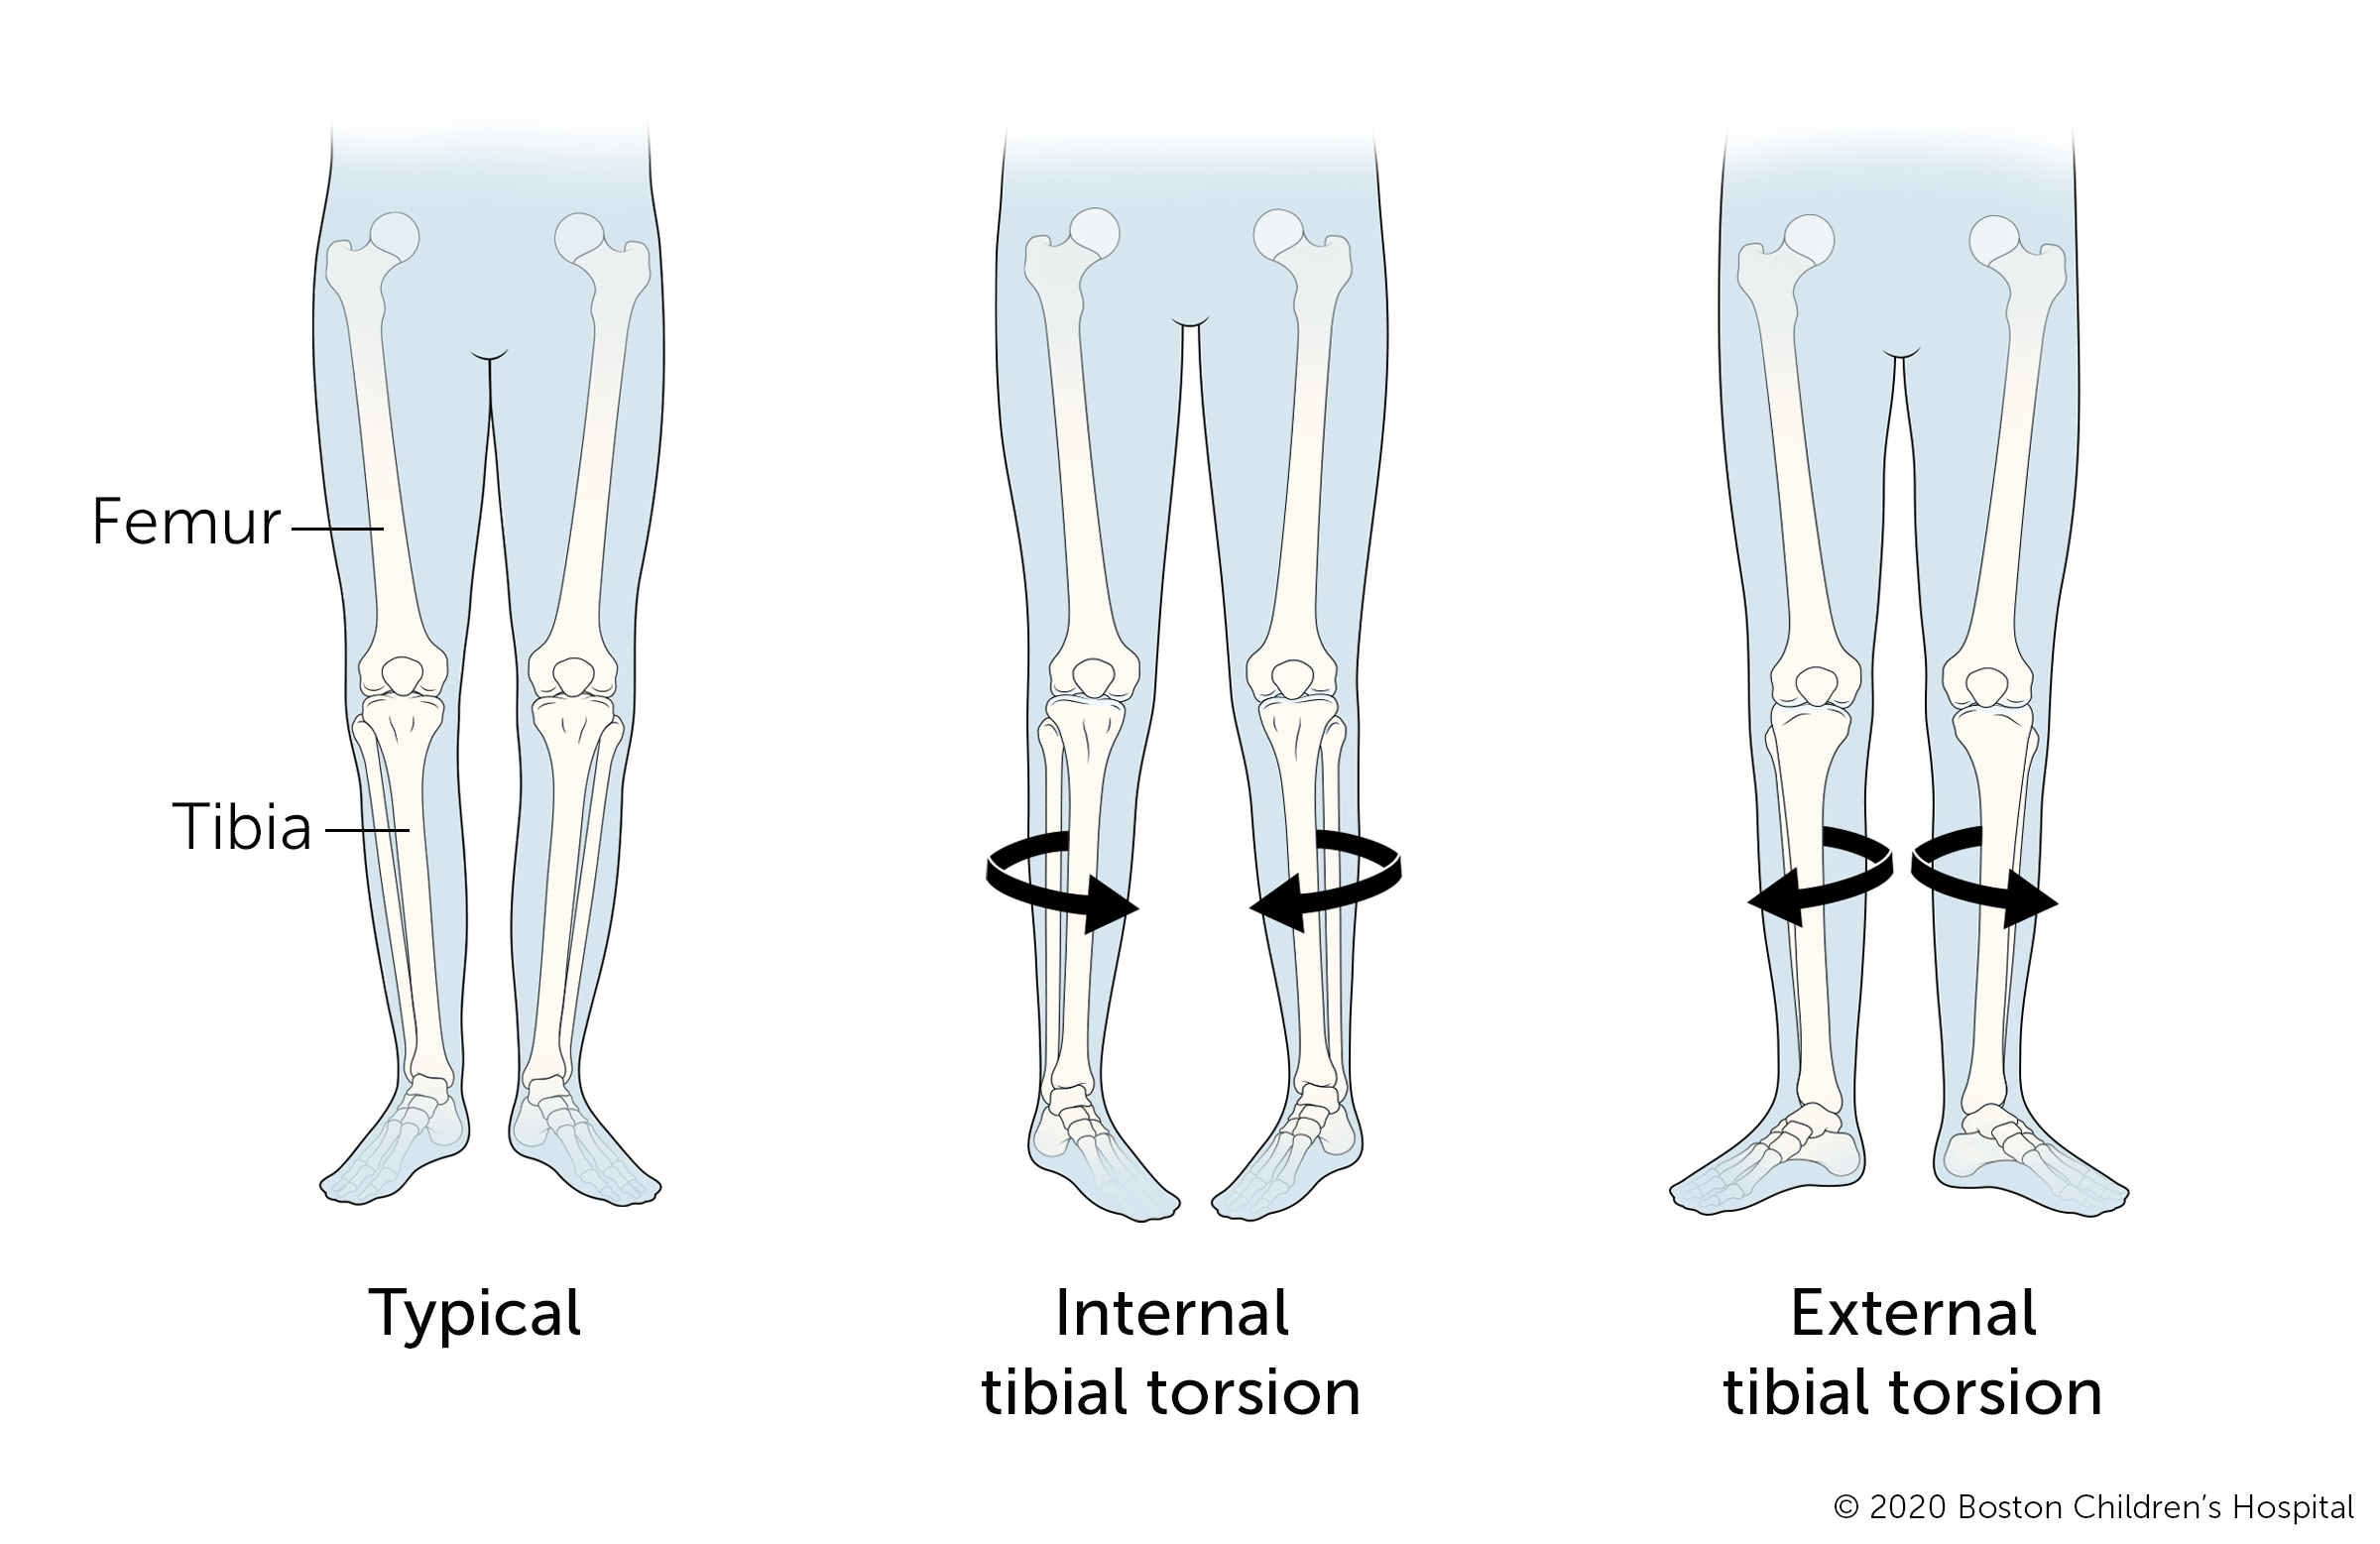

Tibial torsion

Tibial torsion is the turning of a child’s lower leg (tibia) either inward (internal tibial torsion) or outward (external tibial torsion). The condition often improves without treatment, usually before a child turns 4.

Some children with tibial torsion wear a night brace between 18 to 30 months old, but this is not common. Doctors only consider surgery for tibial torsion if a child still has the condition when they are 8 to 10 years old and having significant walking problems.